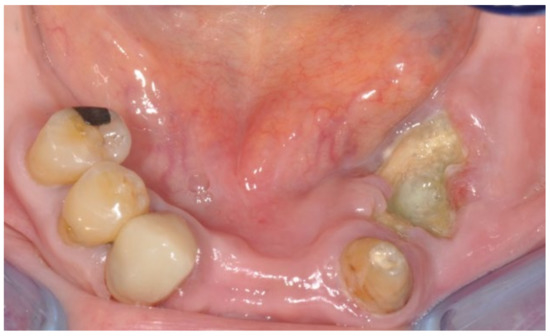

3.1. Clinical Case 1